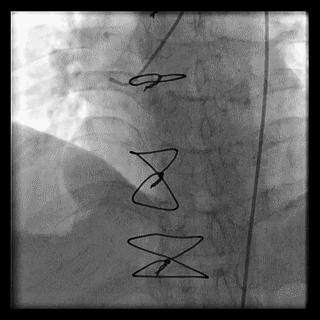

(4)LIMA桥血管造影

首选导管:JR4.0导管

其他导管:如果开口明显成角应选用专用的内乳动脉造影导管

➢ CASE 6

经股动脉途径TIG,非选择造影如果能清晰显影,可不做超选造影